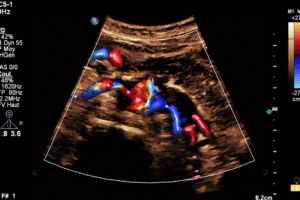

Abdominal Aorta - Vascular Echodoppler